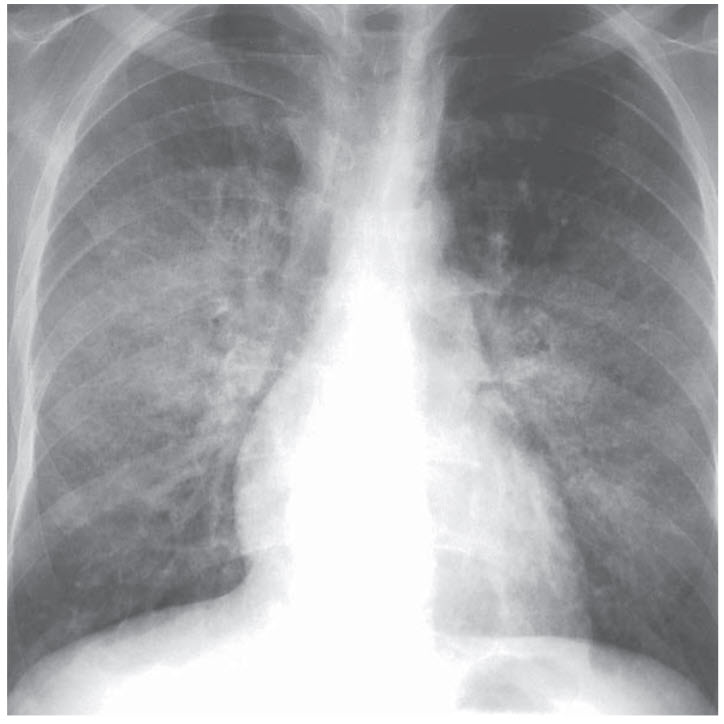

A 48-year-old man presents to the hospital with shortness of breath. He was diagnosed with HIV 2 years ago, refused treatment, and was lost to follow-up. Now he has developed a fever with severe shortness of breath. He has no other known medical problems and takes no medications. He is allergic to sulfa drugs and develops a severe skin rash. His family history is negative for cardiac or pulmonary disease. On examination, his temperature is 38.4°C, blood pressure is 120/80 mmHg, heart rate is 104 beats per minute, respiratory rate is 32 breaths per minute, and oxygen saturation is 84% on room air. An arterial blood gas is significant for a PaO2 of 60 mmHg and a PaCO2 of 28 mmHg. Sputum and blood cultures, as well as other laboratory tests, are pending. The patient’s chest x-ray is shown in Figure below.

: Prednisone and then atovaquone. This patient presents with untreated HIV and likely has a low CD4 count at this time. Patients with CD4 counts below 200 should begin prophylaxis for Pneumocystis jiroveci pneumonia (PCP) with trimethoprim-sulfamethoxazole. Because this patient has a sulfa allergy, alternative treatments include dapsone, pentamidine, or atovaquone. This patient was not taking any prophylaxis and has likely developed PCP, which is indicated by the bilateral interstitial infiltrates on chest x-ray. For patients with a PaO2 <70 mmHg or an A-a gradient >35 mmHg, it is beneficial to treat them with prednisone before antibiotics to reduce the severe inflammatory response to the dying pathogens. (B) Since he has a sulfa allergy, he should not be treated with trimethoprim-sulfamethoxazole; an appropriate alternative treatment is prednisone followed by atovaquone.